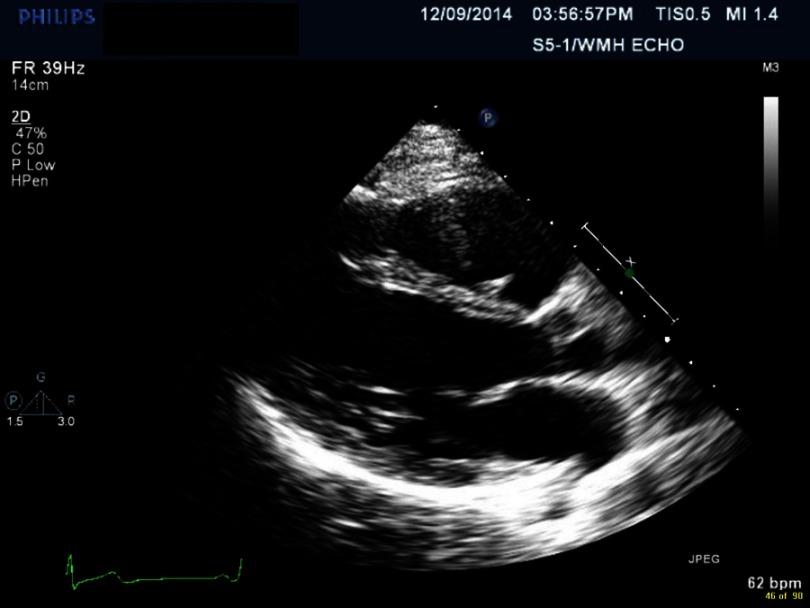

-associated myopericarditis (CAM) has been reported infrequently in the literature. We describe a case of immunocompetent young woman presenting with chest pain, with history of recent travel and diarrhea. Evaluation led to diagnosis of myopericarditis associated with this infection. The patient improved with conservative management. The pathogenesis of CAM remains unknown. Patients present with chest pain, heart failure, pulmonary edema and arrhythmias. Diagnostic evaluation includes EKG, cardiac enzymes, echocardiogram, cardiac MRI and stool culture. Conservative management recommended and routine use of antimicrobial therapy is controversial. CAM is a rare but severe complication of infection. It should be considered as a diagnosis in patients presenting with chest pain with associated gastrointestinal symptoms.